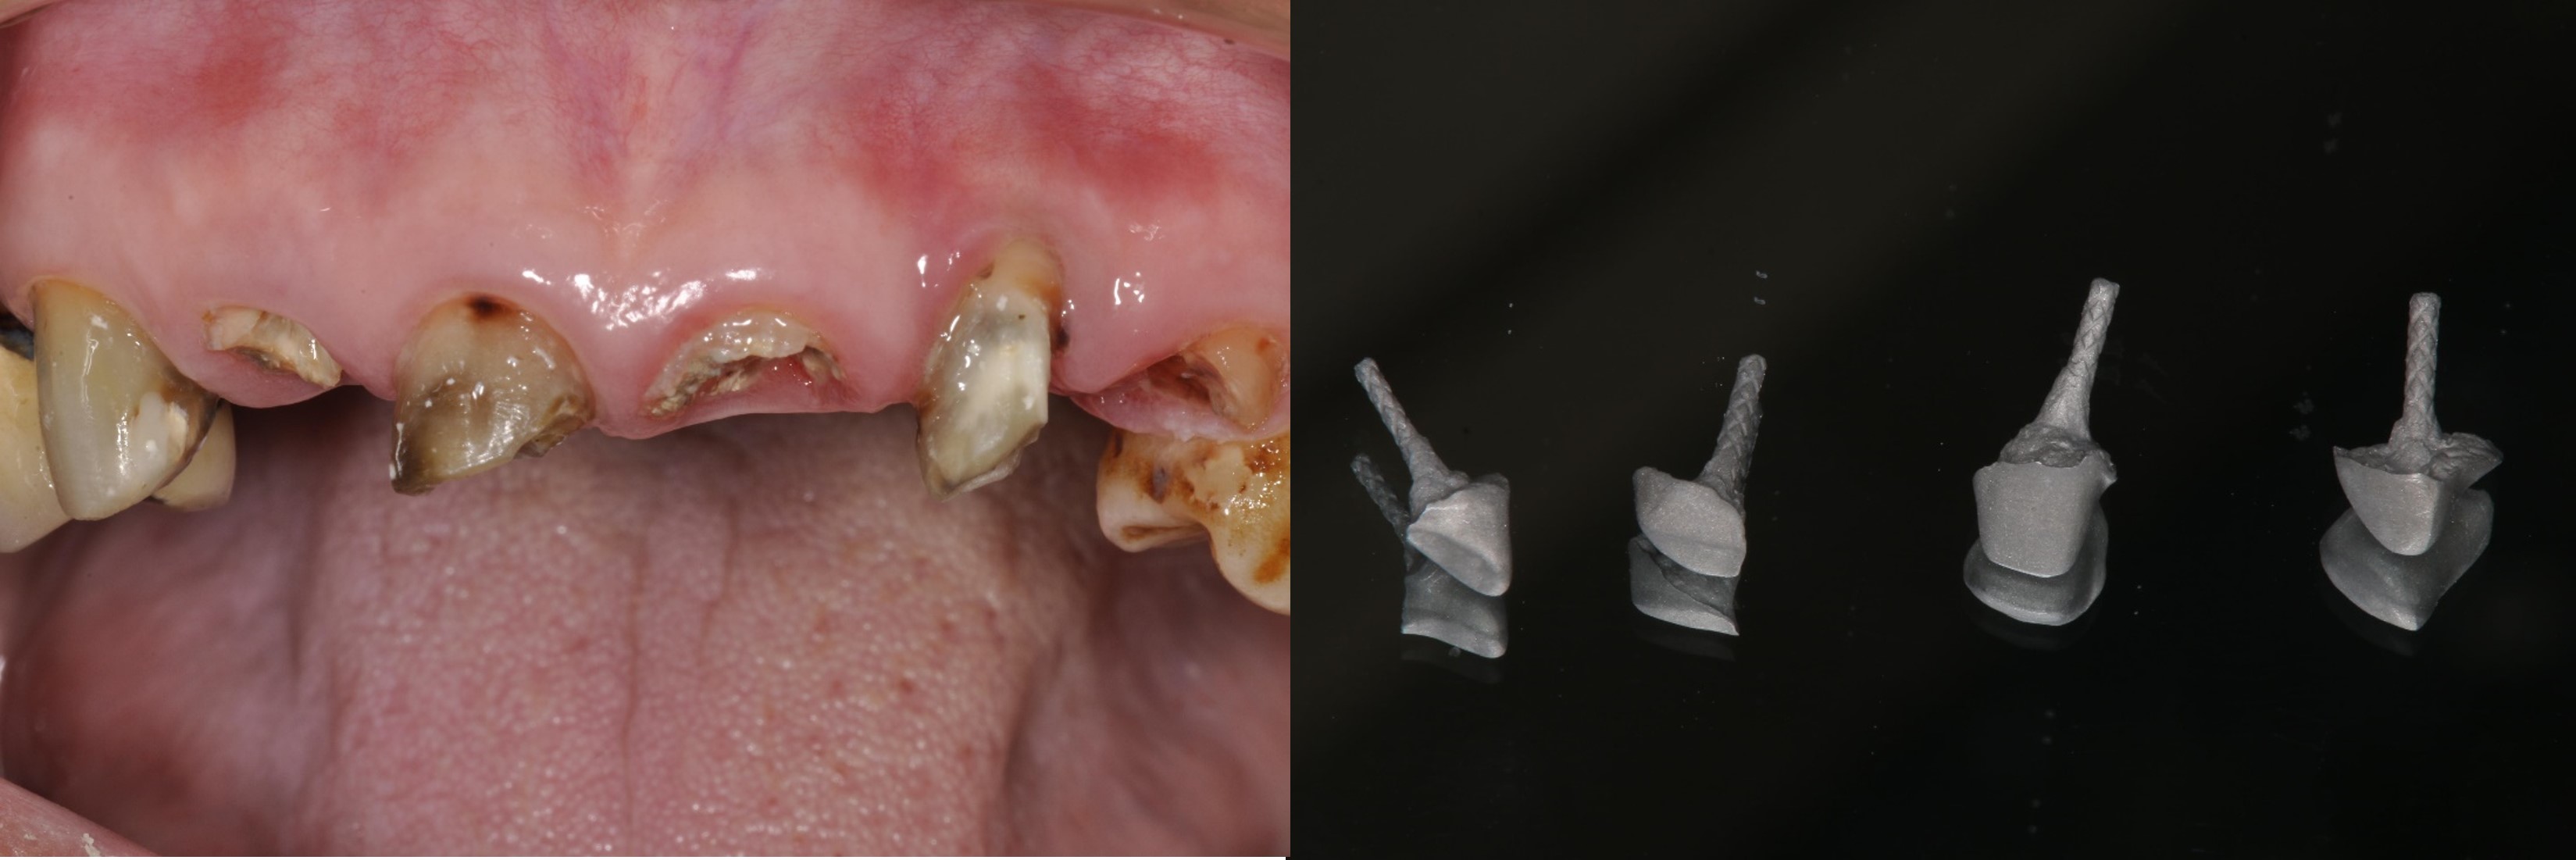

治療前,牙齒再度蛀牙

治療前,牙齒嚴重蛀牙及斷裂